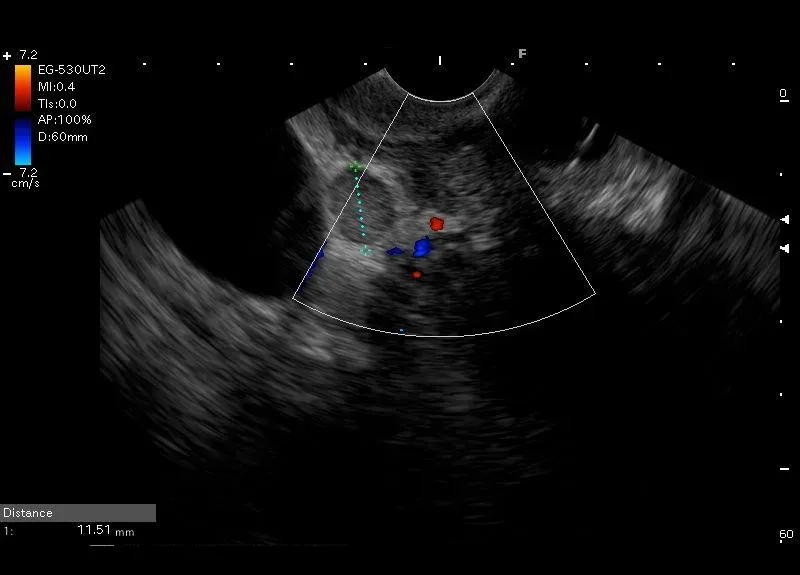

Nieznacznie powiększony węzeł chłonny w okolicy trzustki